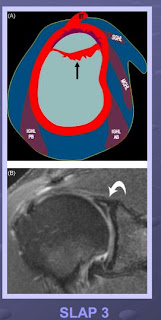

Le diagnostic est radio-clinique: positivité des manœuvre d’appréhension en ABD-RH et laxité G/H au test de Rodineau. Radios suivant le protocole de Bernageau (3 clichés de face et 1 ou 2 profils glénoïdiens) = lésion du rebord glénoïdien antérieur et inférieur (visière de la casquette). L'arthro-scanner visualise en entier le labrum (EDI = lésion inférieure), la capsule et les ligaments gléno-huméraux.